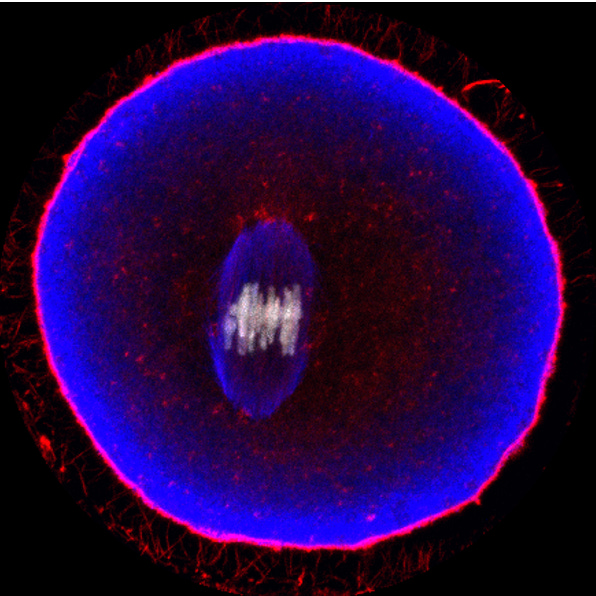

Figure 3 This shows what happens during the time of ovulation when the egg positions its chromosomes (seen in white) on the meiotic spindle (blue, center) and in the moment captured by this image, one can appreciate the forces pulling the chromosomes apart from one another as the egg goes through maturation